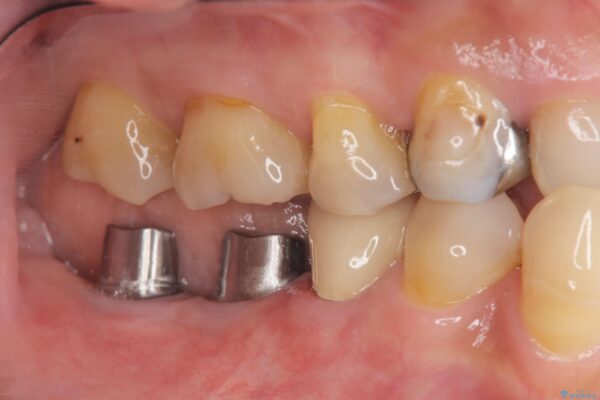

治療中

奥歯から膿のにおいがする インプラントによる機能回復 治療中画像 奥歯から膿のにおいがする インプラントによる機能回復 治療中画像 奥歯から膿のにおいがする インプラントによる機能回復 治療中画像 奥歯から膿のにおいがする インプラントによる機能回復 治療中画像